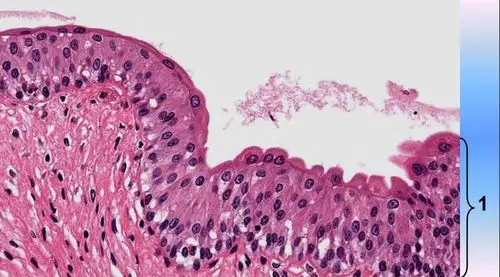

请判断图中1所示的是何种上皮组织?()

显微镜下呈层状鳞状上皮